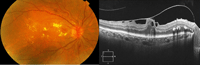

El patrón más frecuente de EMD es el espongiforme (

Figura 1). Se presenta como una hiporreflectividad difusa y homogénea en las capas externas de la retina. El líquido se encuentra inicialmente entre las capas nuclear interna y plexiforme externa; más tarde también puede afectar a las capas plexiforme interna y la capa de fibras nerviosas de la retina hasta afectar a todo el grosor de la retina.

Figura 1. Edema macular diabético con engrosamiento en la retina temporal de tipo espongiforme, y pequeño desprendimiento seroso del neuroepitelio subfoveal. Hialoides posterior parcialmente desprendida.